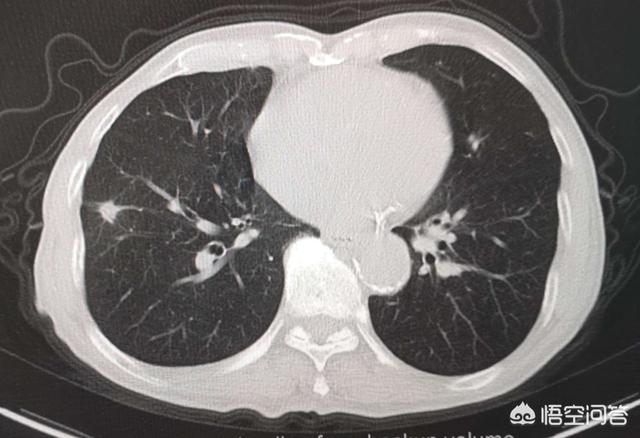

气管和肺泡腔都是空气,密度很低,所以在CT上呈黑色。如上图中的1-7,就是左右主支气管和它的分支,呈黑色,像树枝一样越分越细,所以也被称为支气管树。

那么,题主可能会问:那些白色的条形影是什么?

因为肺部血管内含有血液,密度要高于肺内气体,所以在胸部CT上呈现白色条形影。

这些血管断面,会不会误认为肺结节呢?

有读者提到过这个问题,答案是不会的!因为观察肺部影像是动态连续层面观察,血管断面连起来看呈条形,而不是孤立性结节。